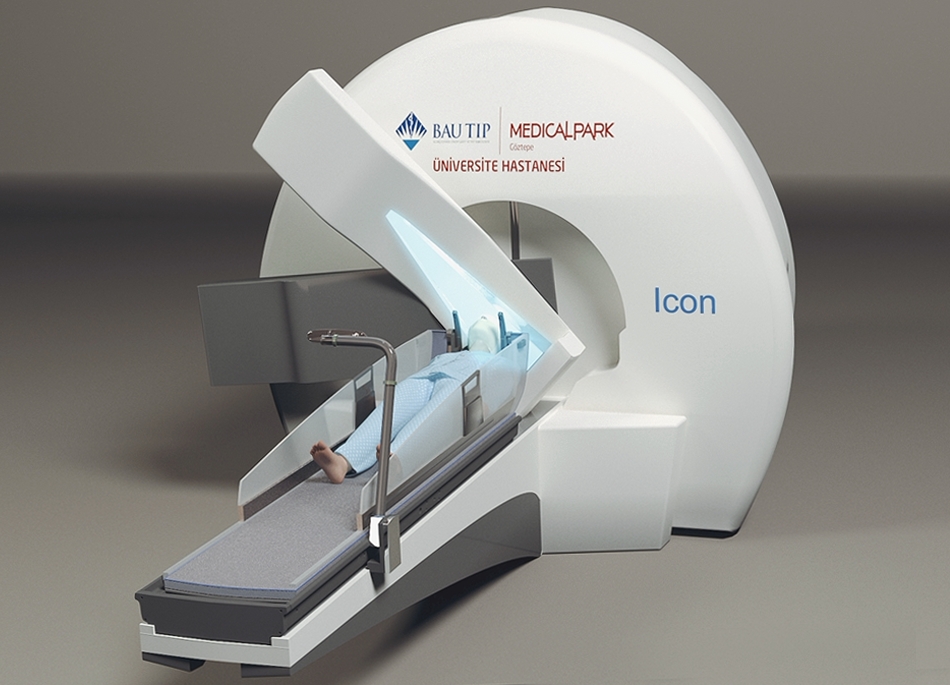

3d Medikal Tanıtım Filmleri - Medikal sektör için 3D ilaç tanıtım filmleri.